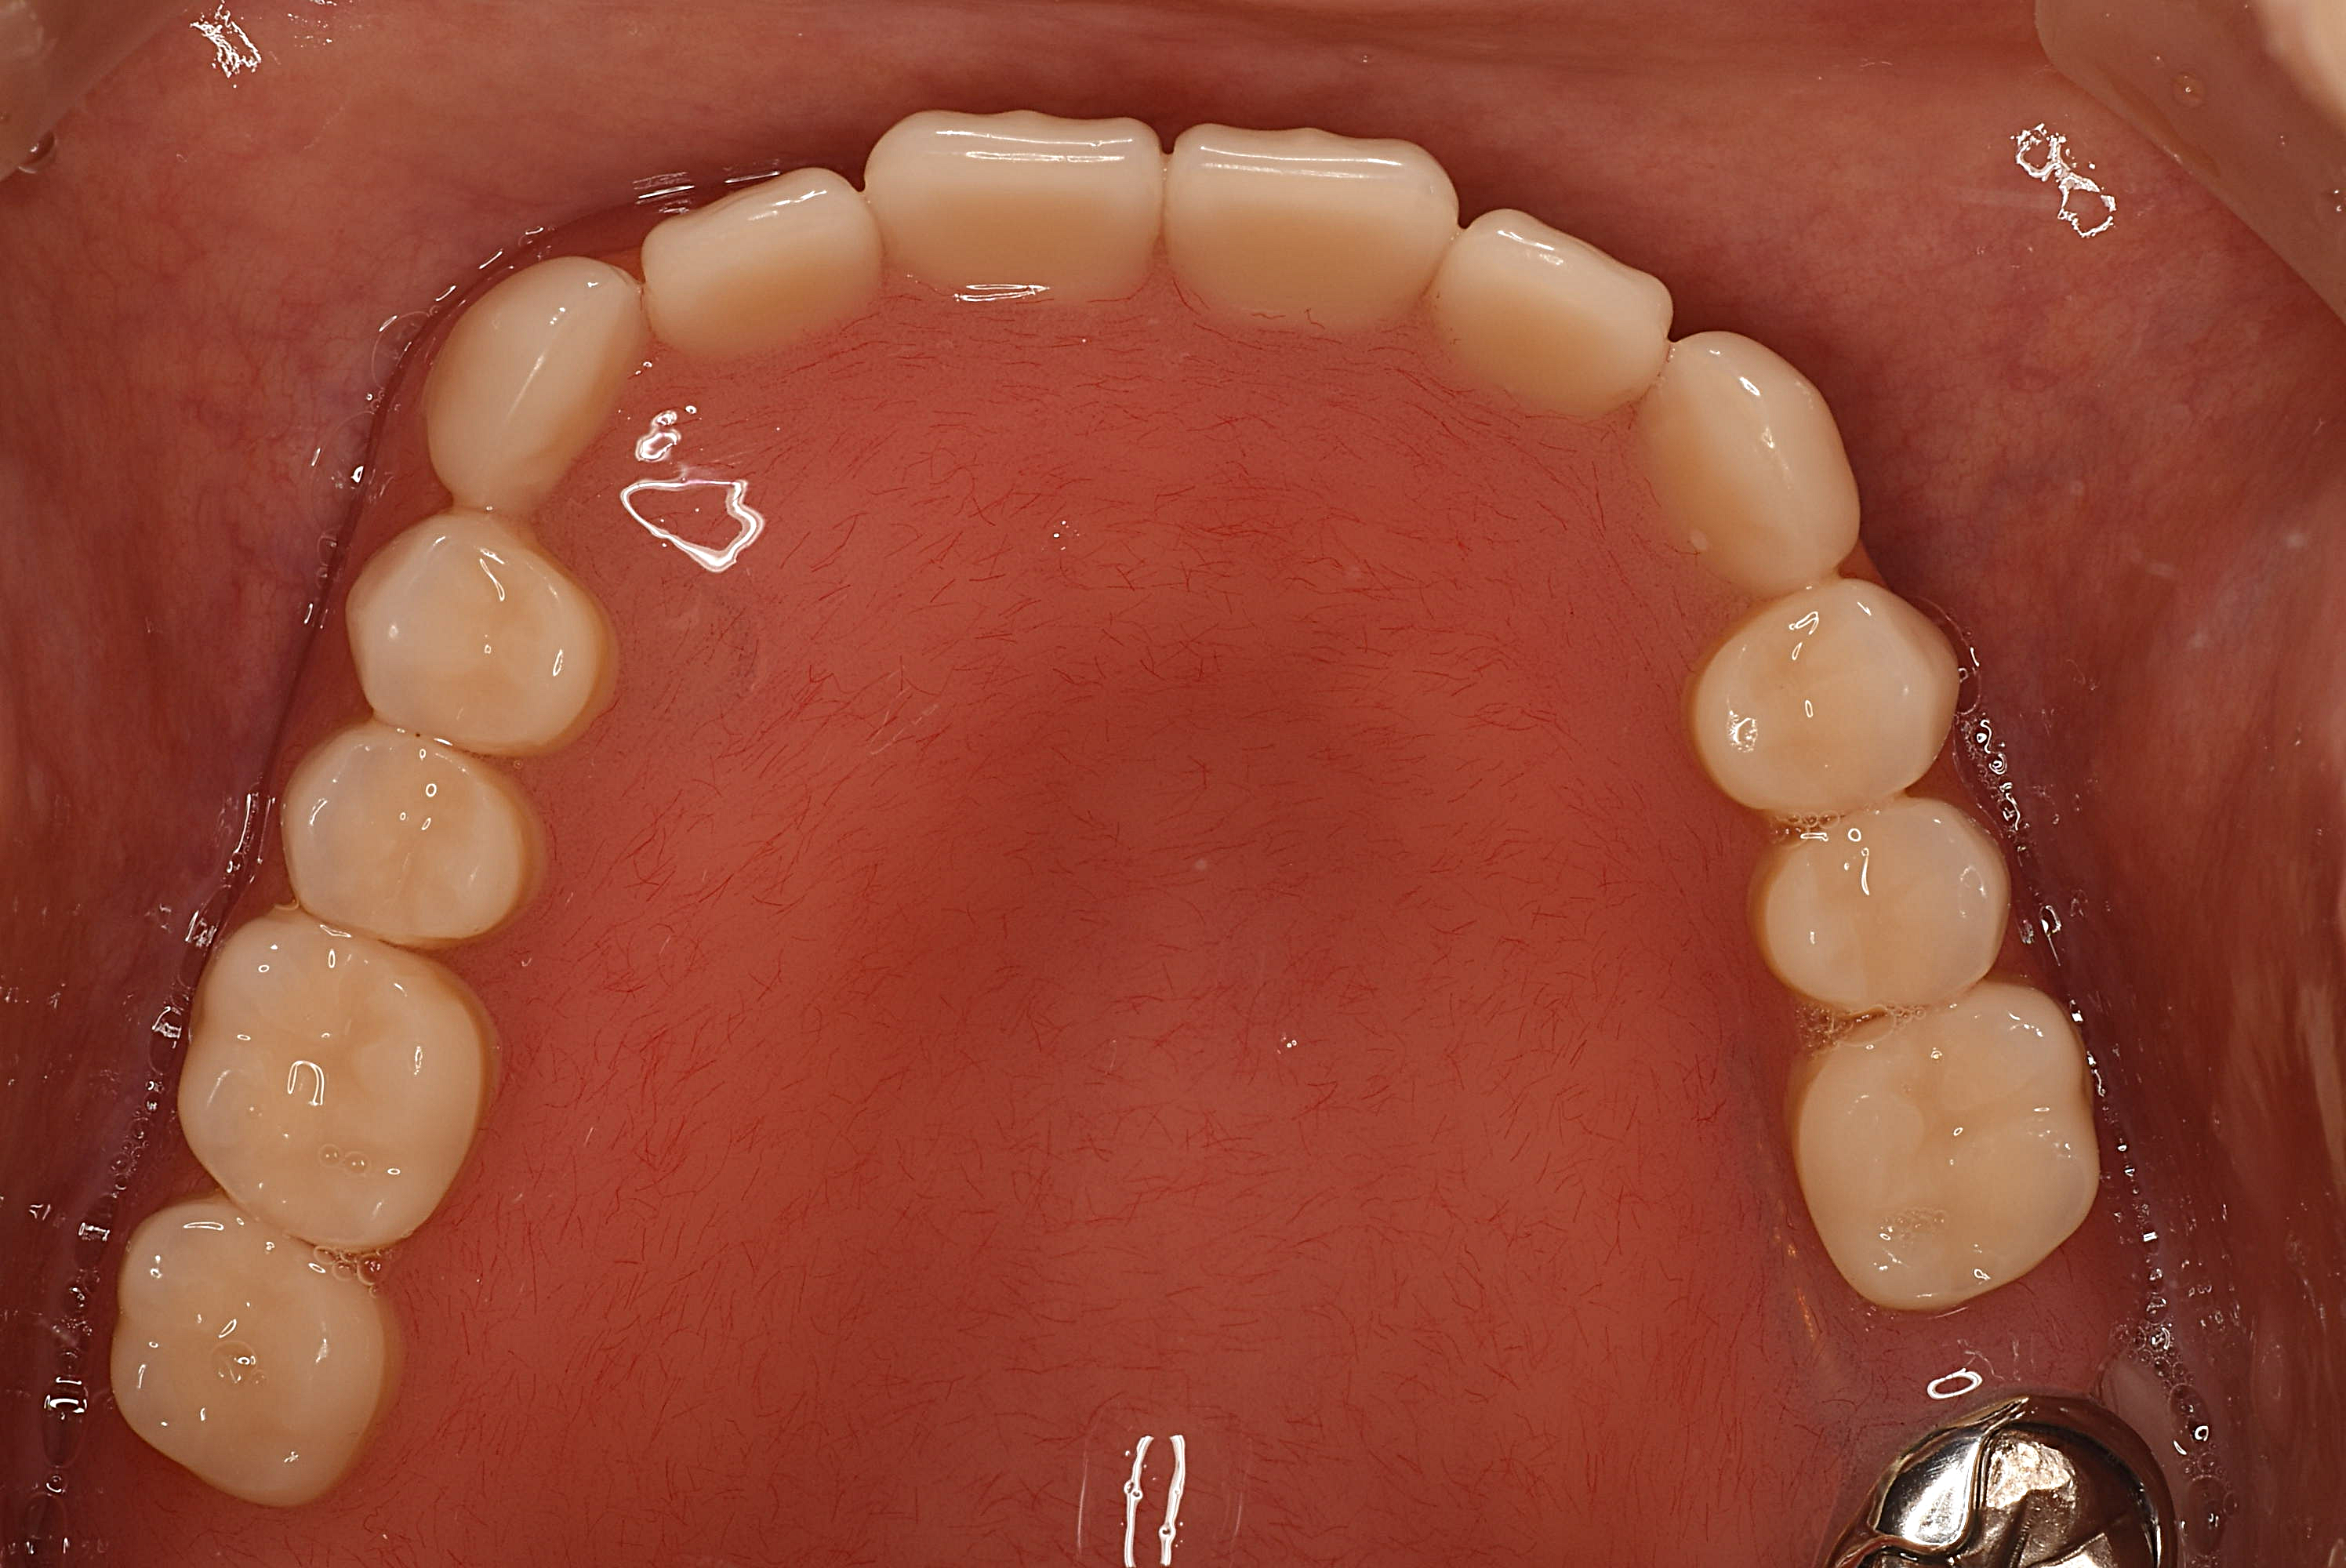

⇧残念ながら保存できない歯は抜歯となり、失った歯の代わりに入れ歯を作製し、噛める環境に回復しました。入れ歯は完全に発音を回復するというのは難しいですが患者さんは満足されています。